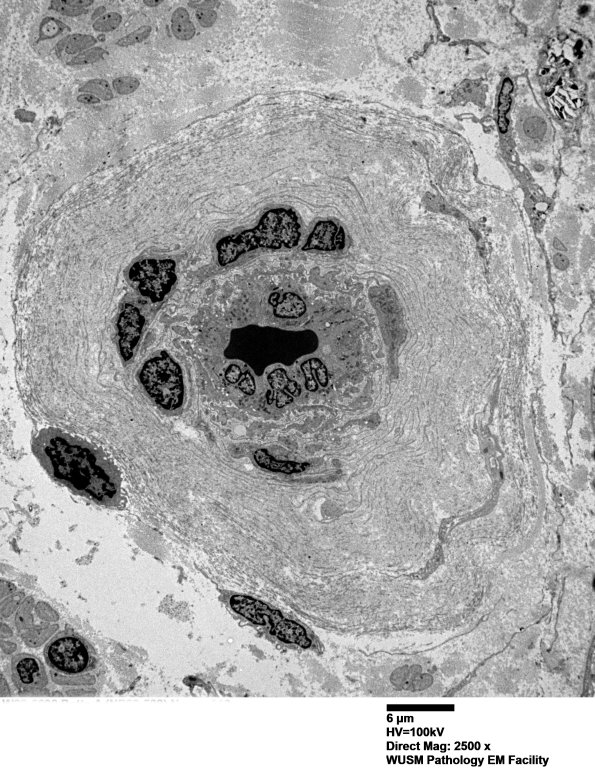

Thickening of this vessel wall consists of accumulated basal lamina fragments and collagen. Several individual inflammatory cells may be present. (electron micrographs)